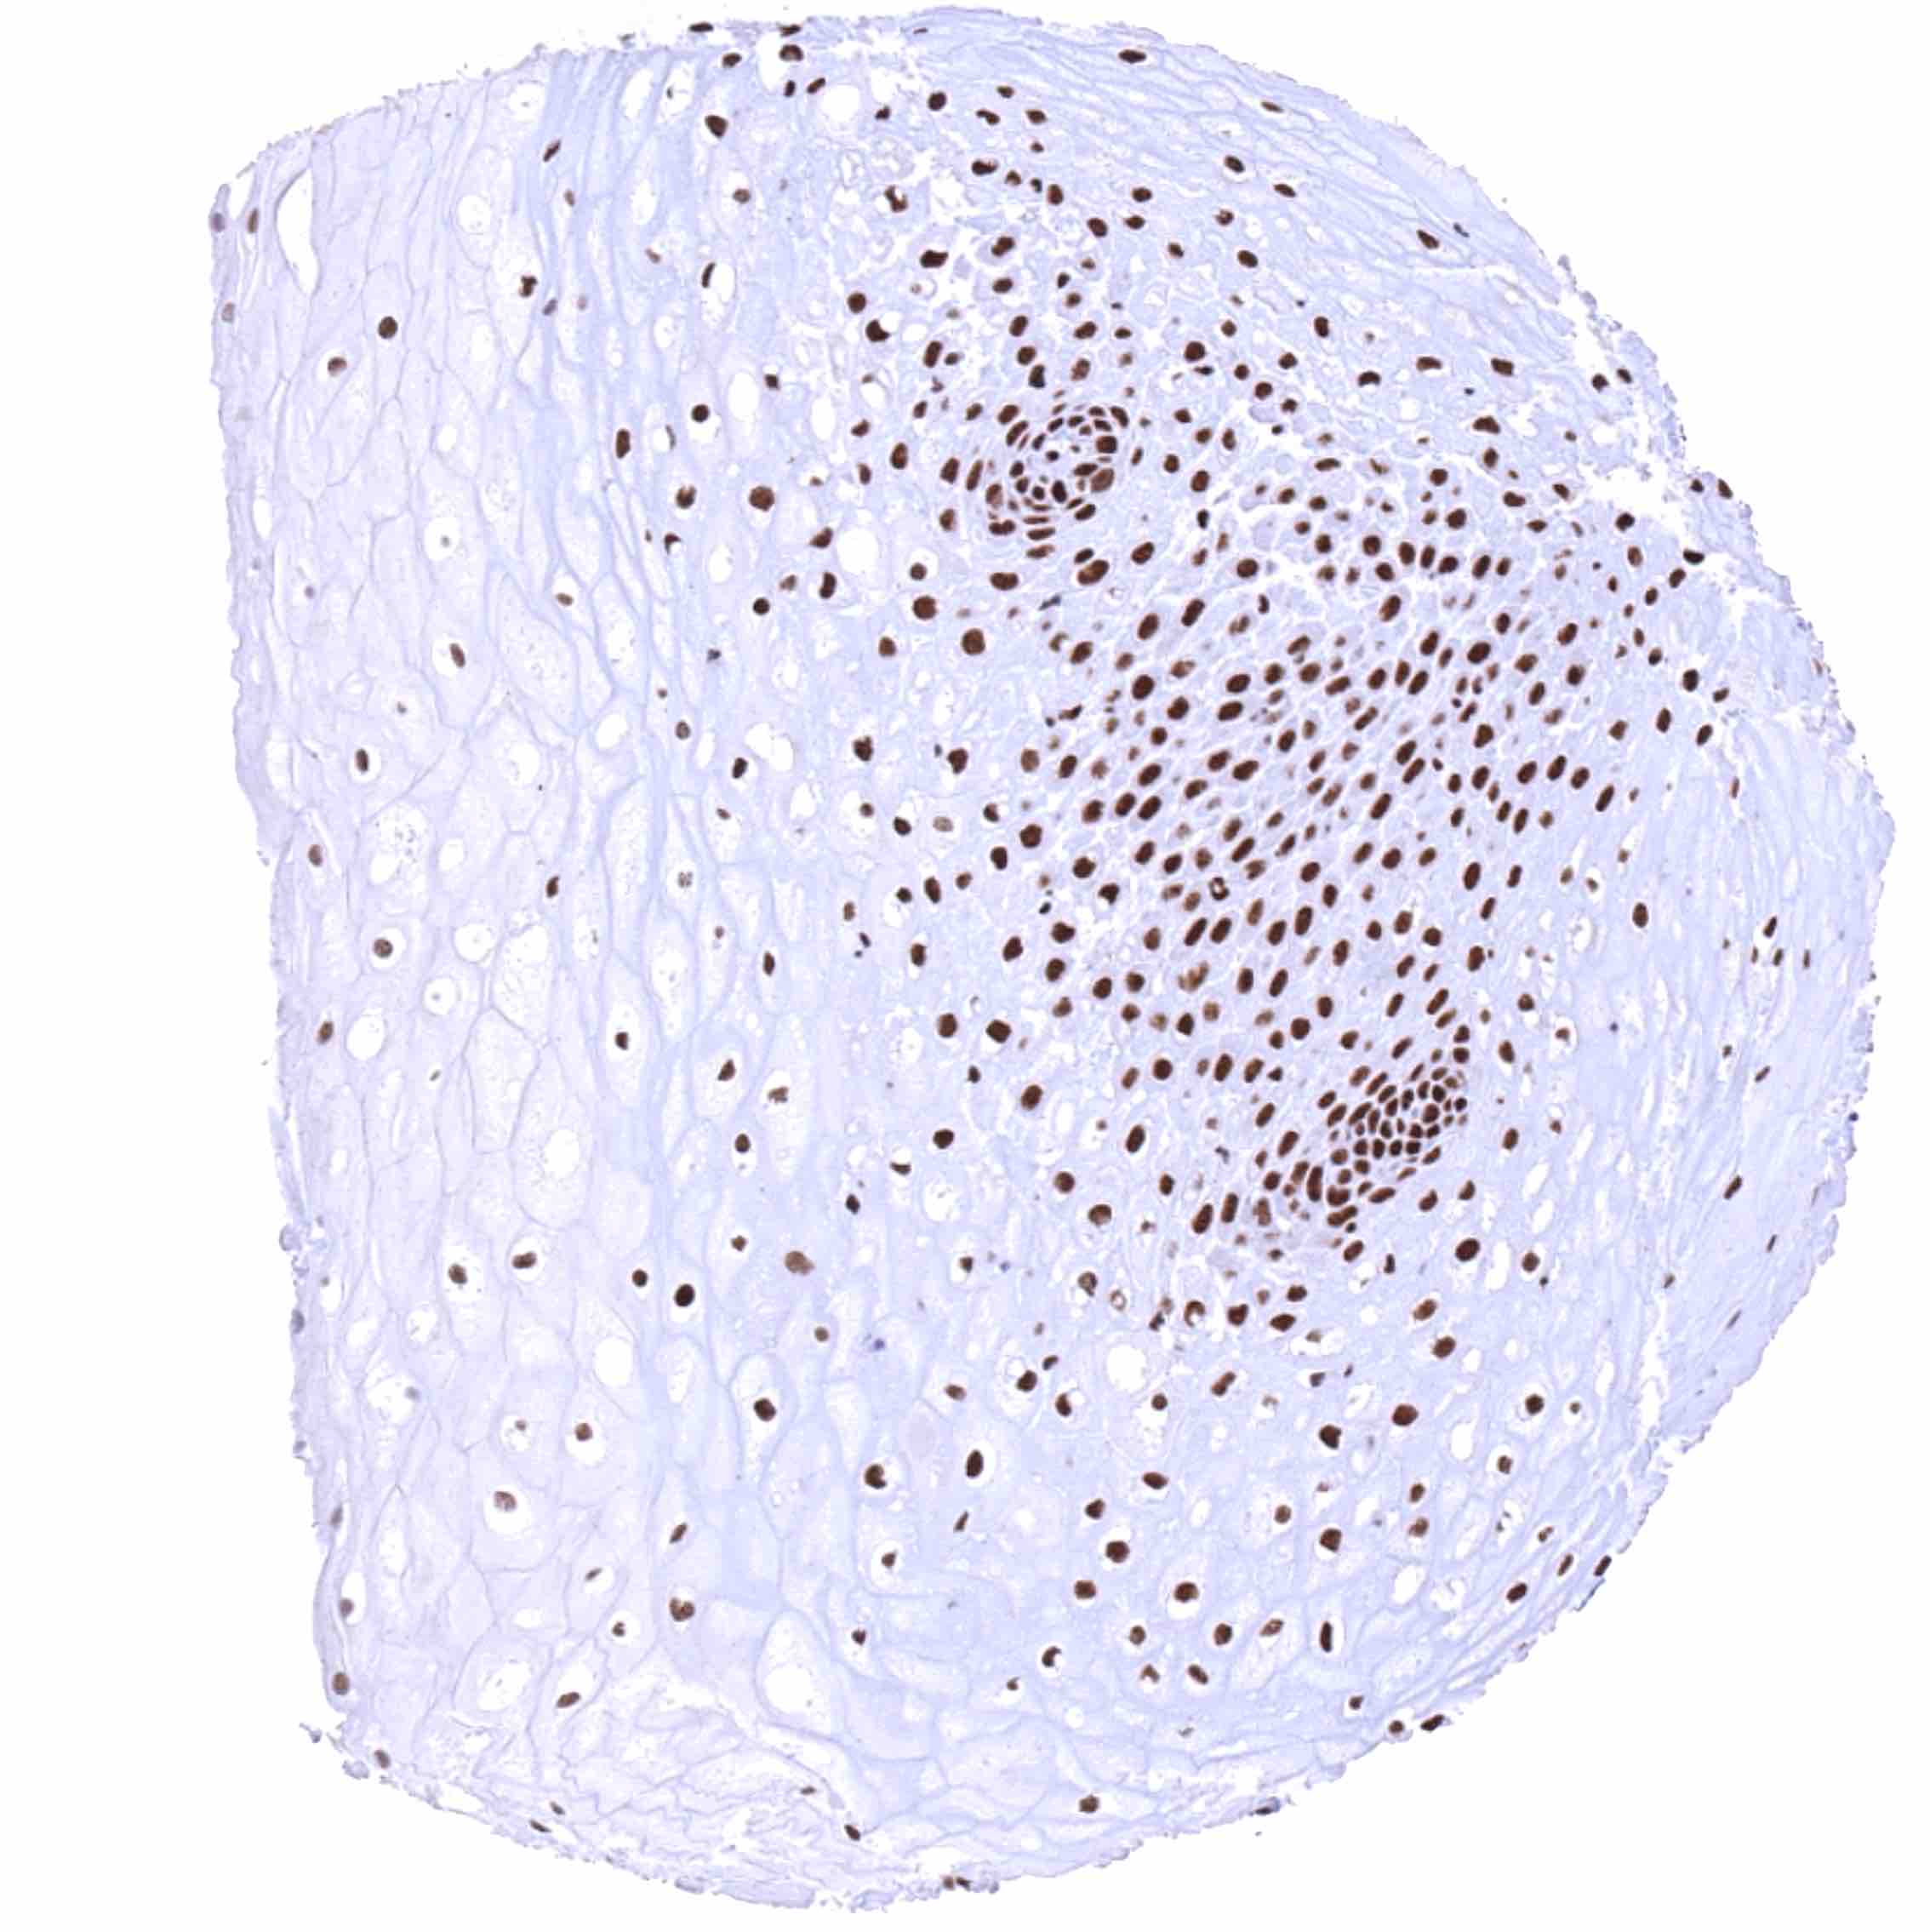

Esophagus, squamous epithelium – Distinct nuclear BRD4 staining of squamous epithelial cells with a slight decrease of the staining intensity towards the most superficial cell layers.